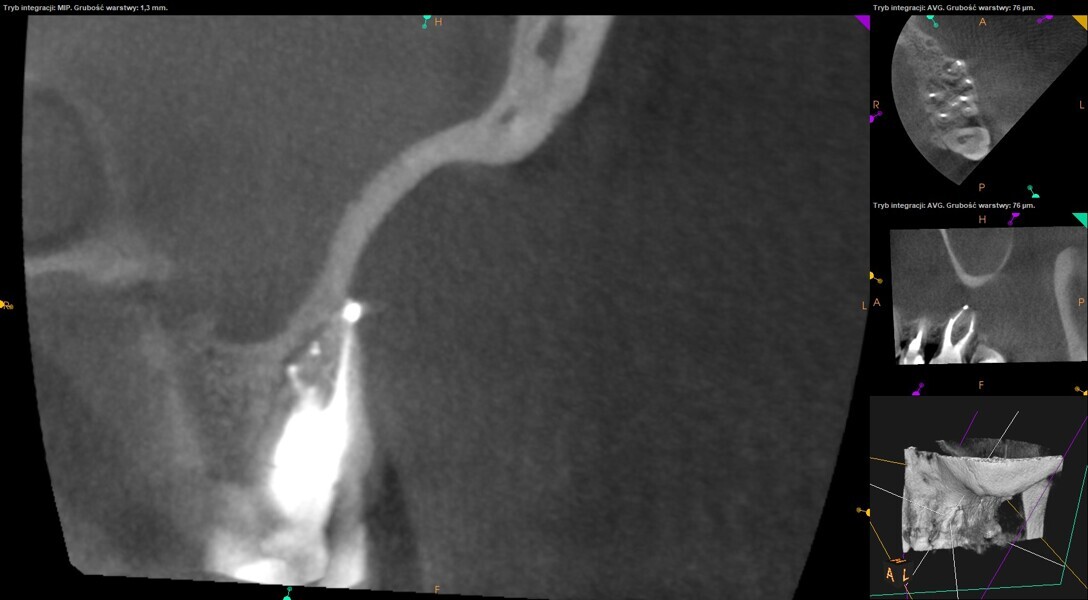

Post-op radiograph of a mandibular molar. (All Images: Bartłomiej Karaś)

Case 2 (Figs. 27–36)

A 25-year-old female patient presented to the office owing to constant pain related to the mandibular left first molar. Pulp necrosis was diagnosed. After the emergency appointment, the patient was referred for complete treatment. The tooth was treated in the same manner as described in the previous paragraphs. After creation of the access cavity, the orifices were located. In the root chamber, the orifices of the MB, mesiolingual, DB, distomesial and distolingual canals were present. After pre-flaring and preparation of the middle third, the LPE enhanced irrigation protocol with the SkyPulse laser was performed. After the irrigation protocol in the mesial root, the irrigants started to flow between lingual and buccal canals. Such an observation suggested to the operator that some space in the isthmus had been created. It is worth mentioning that at this stage apical enlargement was not performed. Final preparation of all five canals was performed with the reciprocating file, and the final irrigation protocol was performed as in the previous case. The radiograph clearly revealed that the isthmus space was filled with the sealer. The radiograph and CBCT image revealed that there were four portals of exit in the mesial root.